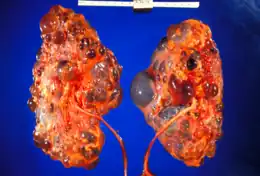

Reins polykystiques gravement affectés enlevés au moment de la transplantation